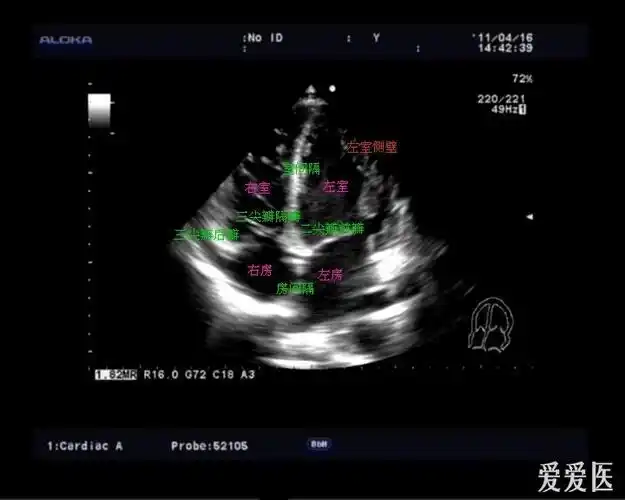

图文详解 | 心超切面不会打?看这一篇就够了!

【零基础学心超,一天一图一讲解001】之胸骨旁左心室长轴切面

经典心脏超声切面图及解剖解释